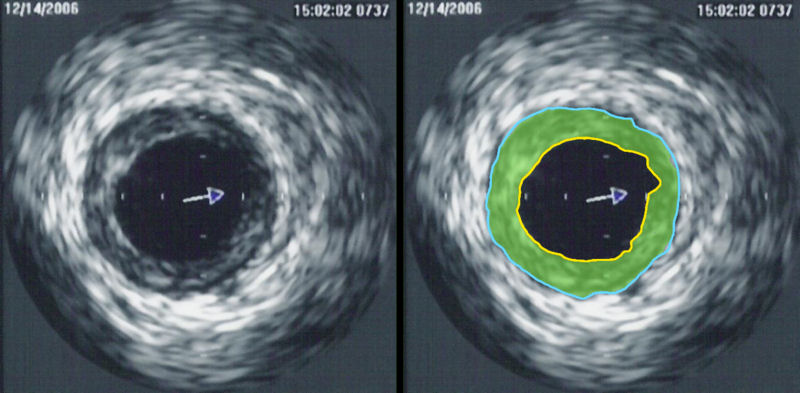

Intravascular ultrasound image of a coronary artery

Source: IVUS of CAD.png Date: 7 July 2007 Author: Karthik Sheka, M.D. Licence: Creative Commons Attribution-Share Alike 2.5 Generic